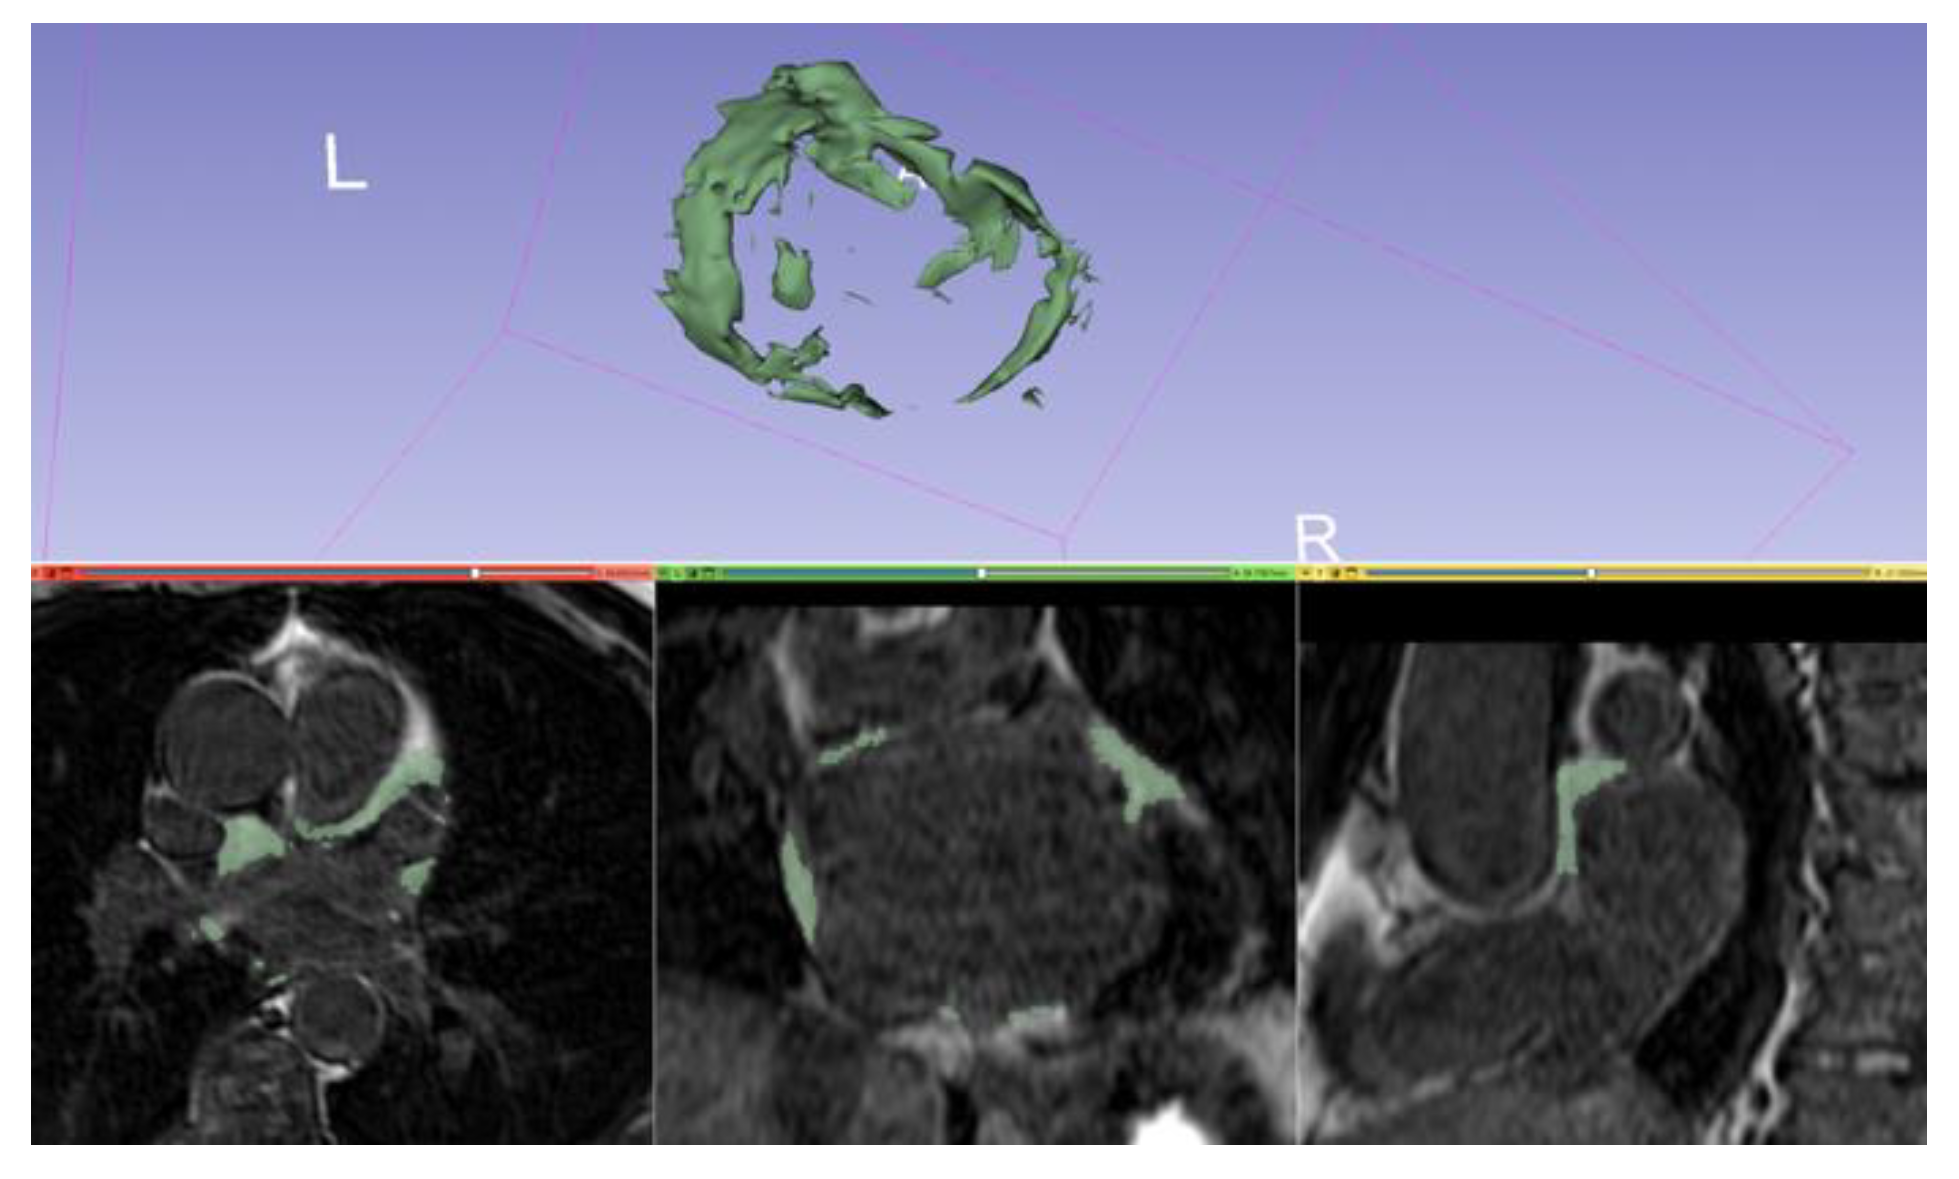

5. CMR-Guided Ablation

- The DICOM images are imported in a dedicated workstation, and they are segmented;

- During the procedure the LA is electroanatomically mapped using a dedicated catheter;

- The anatomic CMR map is merged with the electroanatomic one to obtain a hybrid map; and

- Finally, the ablation catheter is navigated in the LA using a hybrid map [72].